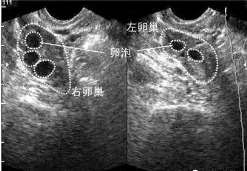

多囊卵巢综合征怎样确诊?PCOS的诊断标准主要包括以下三个方面:1 .排卵或不排卵,表现为月经趋势异常,可作为PCOS的诊断标准;2.超声检查显示卵巢多囊改变,是PCOS最准确的诊断方法;3.雄激素过高,有多毛问题,长痘